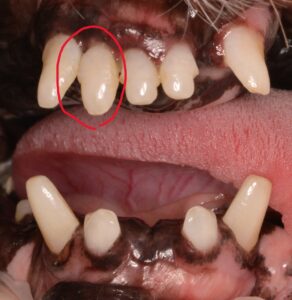

触診では上画像で赤丸をしている右上顎の2番目の歯(102)が他の歯と比較しても大きく揺れていました。

歯周病が原因で歯が揺れることもありますが、歯肉の状態は他の歯と変わらないため、1本だけが折れている可能性も考慮し歯科処置をすることにしました。